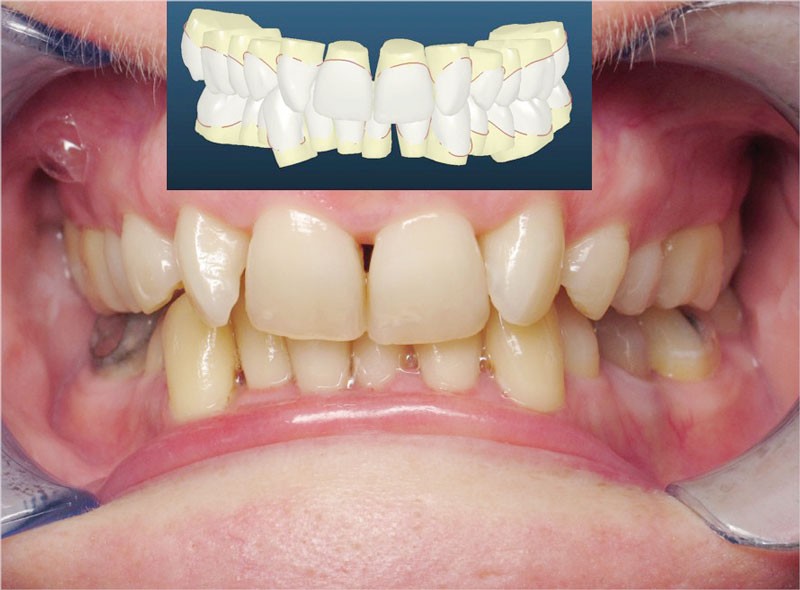

Nous lui avons donc proposé un traitement d’alignement avec maintien des 14 et 24 en position de 13 et 23 et optimisation du torque pour favoriser un développement des arcades et chercher à améliorer le sourire et le soutien labial.

La patiente donne son accord pour un appareillage Damon Insignia métal qui permet une individualisation complète des brackets dans les 3 sens de l’espace.

Un appareillage Damon métal a été mis en place, réalisé à partir d’un set up numérique Insignia pour obtenir un contrôle précis des torques et de la forme d’arcade et réduire le temps de finition grâce à un collage indirect très précis.

L’objectif, en utilisant la technique Insignia est de réduire le temps de traitement de 28 à 18 mois avec 12 rendez-vous (fig. 5 à 14).